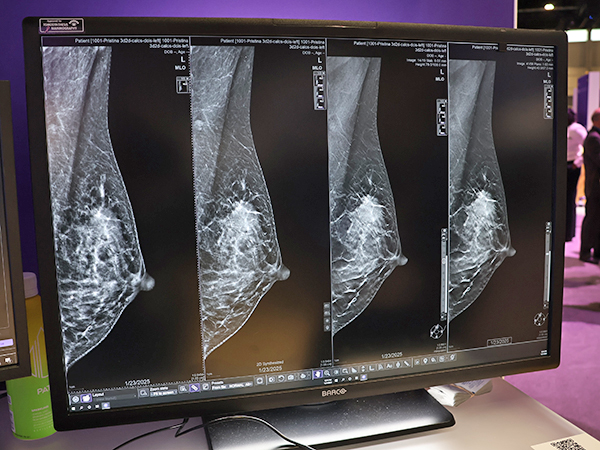

「Pristina Recon DL」

デジタルマンモグラフィ「Pristina Via」の

最新バージョン(薬機法未承認)

GE HealthCare(GEヘルスケア)のWomen’s Healthコーナーでは前回発表したデジタルマンモグラフィ「Pristina Via」の最新バージョン(薬機法未承認)のアンベールイベントを行い,新たに搭載されるディープラーニング技術を応用した3Dマンモグラフィ画像再構成技術「Pristina Recon DL」(薬機法未承認)をアピールした。RSNA 2025前に,米国食品医薬局(FDA)の承認を得たばかりの新技術で,乳房トモシンセシス(DBT)において,低線量での撮影でも高画質画像を得られる。ディープラーニング技術は高精度な3D画像再構成を行い,ノイズを抑えてアーチファクトを抑制する。Pristina Recon DLでは,合成2D画像とplaneとslabの3D画像の3種類の画像を出力する。従来,トモシンセシス画像の読影には時間を要していたが,Pristina Recon DLによって読影の負担軽減につながることが期待される。

「Pristina Recon DL」(薬機法未承認)により微細な石灰化や腫瘤の描出能が向上